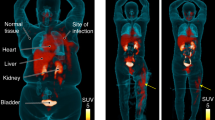

PET/CT imaging in mice and rats

MicroPET/CT imaging of Balb/c mice injected with 68Ga-PVD-PAO1 confirmed the data from ex vivo biodistribution studies. 68Ga-PVD-PAO1 was rapidly cleared from the bloodstream with the major excretion route via kidneys (Supplementary Fig. S2B). PET/CT imaging in the rat respiratory infection model showed focal accumulation of 68Ga-PVD-PAO1 in the lung (Fig. 5B). No uptake in the lung region was detected in non-infected rats in which the only visible organs were the kidneys and bladder (Fig. 5A). In vivo specificity of 68Ga-PVD-PAO1 for Pseudomonas infection was studied in the mouse muscle infection model. PET/CT images summarized on Fig. 6 display specific accumulation of 68Ga-PVD-PAO1 in P. aeruginosa infection and much better biodistribution compared to radiopharmaceuticals clinically used for infection imaging. 68Ga-PVD-PAO1 showed not only great in vivo specificity but also high sensitivity enabling to detect Pseudomonas infection in the dose of 5 CFU (Fig. 7).

Static PET/CT imaging (coronal slices) of 68Ga-PVD-PAO1 in Balb/c mice muscle infection model with different level of infection load 45 min post injection. Standard uptake values (SUV) in P. aeruginosa (P.a.) infected muscles were calculated by PMOD software (PMOD Technologies Ltd., Zurich, Switzerland) and were 6.01 ± 0.70%ID/g for 5 × 107 CFU/dose; 4.60 ± 0.58%ID/g for 5 × 103 CFU/dose and 0.82 ± 0.22%ID/g for 5 CFU/dose.

Discussion

Novel reliable approaches enabling specific, sensitive and early diagnosis as well as rapid monitoring of infectious diseases are constantly searched for also in the field of nuclear medicine imaging18. Currently the diagnosis of infection with radiopharmaceuticals is mainly performed with 99mTc- or 111In-labelled leukocytes, 67Ga/68Ga-citrate, 99mTc-diphosphonates and 18F-FDG19. However, all of these compounds lack the specificity to discriminate among different infectious pathogens and even between infectious and non-infectious inflammation. The limitations of 18F-FDG and 68Ga-citrate in terms of pharmacokinetics and specificity were demonstrated in Fig. 6. Recently, various attempts were made to develop specific nuclear imaging agent for infection detection including radiolabelled antimicrobial agents (e.g. peptides, antibiotics), monoclonal antibodies, cytokines, nucleoside analogues (e.g. fialuridine), saccharides (e.g. fluorodeoxysorbitol, maltohexaose, maltose, trehalose), oligomers, polyethyleneglycol liposomes, fluorophores and siderophores18,20,21,22. However, none of these probes was translated to routine clinical practice so far. Imaging agent with clinical translation potential is expected to have the following unique characteristics: (i) high binding affinity to target, (ii) high specificity to target, (iii) high sensitivity, (iv) high contrast, (v) high in vivo stability, (vi) low immunogenicity and toxicity and (vii) economical and production feasibility23. We believe that from the agents currently under investigation, especially siderophores hold the promise to fulfil these criteria.

It is known that numerous microorganisms possess specific uptake systems not only for native siderophores, but also for siderophores synthesized exclusively by other pathogens, so called “xenosiderophores”35. Therefore, in vitro uptake studies of selected 68Ga-siderophores in P. aeruginosa and 68Ga-PVD-PAO1 in different microorganisms were performed. None of tested 68Ga-siderophores was significantly taken up by P. aeruginosa and the uptake of 68Ga-PVD-PAO1 was highly specific for P. aeruginosa cultures. In animals, 68Ga-PVD-PAO1 showed excellent pharmacokinetic properties with rapid renal elimination from non target tissue, selective accumulation in infected tissues and great sensitivity enabling the detection of only five viable cells of P. aeruginosa. Moreover, 68Ga-PVD-PAO1 displayed better specificity and pharmacokinetic properties than other, clinically used radiopharmaceuticals.